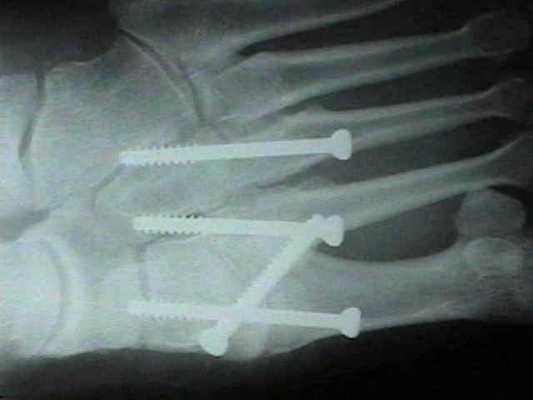

При смещении более 2 мм, нестабильности при функциональных тестах – рекомендовано открытое устранение вывиха с жёсткой фиксацией винтами или пластинами. Используются один или два продольных доступа в 1 и 2 межплюсневых промежутках. После обнажения первого предплюсне-плюсневого сустава первым этапом устраняется межклиновидная нестабильность, вторым этапом устраняется предплюсне-плюсневая нестабильность. В послеоперационном периоде сразу начинается разработка активного объёма движений. Нагрузку на стопу начинают постепенно, с тем чтобы полностью её восстановить к 6-8 неделе. Удаление спиц Киршнера производится через 6-8 недель, компрессирующих винтов через 3-6 месяцев. Возвращение к полной физической активности не ранее 9-12 месяцев после операции.

Открытое вправление вывиха, трансартикулярная фиксация 1-2-3 предплюсне-плюсневых суставов винтами.

Даже при изолированном связочном повреждении со значительной нестабильностью рекомендуется артродез 1-2-3 предплюсне-плюсневых суставов. Данный вид лечения характеризуется меньшим количеством осложнений (таких как посттравматический артроз и миграция металлофиксаторов) чем открытая репозиция с внутренней фиксацией. После операции рекомендуется ношение циркулярной гипсовой иммобилизации 6 недель, ходьба без нагрузки. Постепенное увеличение осевой нагрузки с 6 по 12 неделю.

В случаях этого повреждения показано оперативное лечение, открытое устранение подвывиха основания 2 плюсневой кости с фиксацией винтом. Устранение подвывиха производится из доступа в 1 межплюсневом промежутке, рубцовая ткань и остатки связки могут интерпонировать сустав, тогда потребуется их удалить. После вправления производится предварительная фиксация спицей и рентгенологический контроль.

Затем устанавливается винт соединяющий основание 2 плюсневой кости и медиальную клиновидную кость.

После осмотра в отделении ортопедии №2 ГКБ №13 принято решение о проведении операции – открытому устранению вывиха, артродезе 1-2-3 плюсне-клиновидных суставов, 1 межклиновидного сустава при помощи винтов и пластины, трансартикулярной фиксации спицами 4-5 плюсне-клиновидных суставов.

Вершиной, ключом, блокирующим клином – в общем главной частью сустава Лисфранка является 2 плюсне-клиновидный сустав. По этой причине мы предпочитаем начинать фиксацию именно с него. Для артродеза используем винты с направленной в разные стороны резьбой FT Arthrex диаметром 4 мм. Они позволяют создать мощную межфрагментарную компрессию, а за счёт глубокой резьбы очень надёжно фиксируются в кости.

После восстановления 2 луча выполняем артродез межклиновидного сустава и 1 плюсне-клиновидного сустава. Учитывая что основная нагрузка ложится на 1 луч, дополнительно стабилизируем его при помощи пластины.